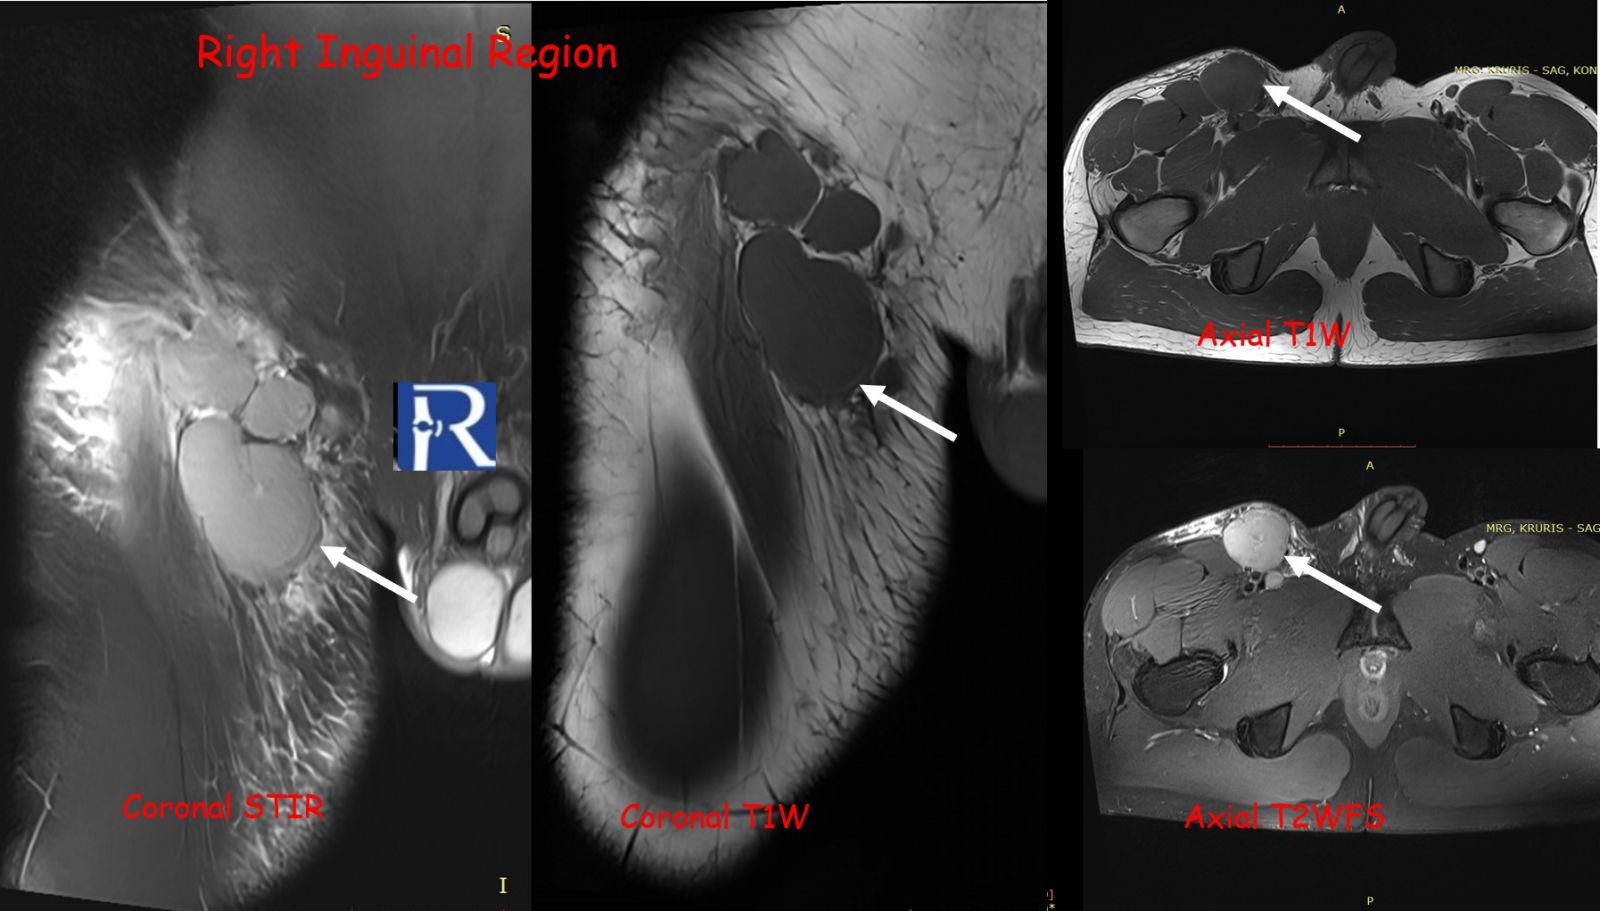

The lesion exhibited limited cortical destruction, yet extensive soft-tissue extension. Multiple conglomerate inguinal and pelvic lymph node enlargements were also identified, demonstrating signal characteristics similar to those of the primary lesion.

These imaging findings—particularly the absence of periosteal reaction, intermediate T2 signal, and marked DWI restriction—favored the diagnosis of lymphoma over Ewing sarcoma.